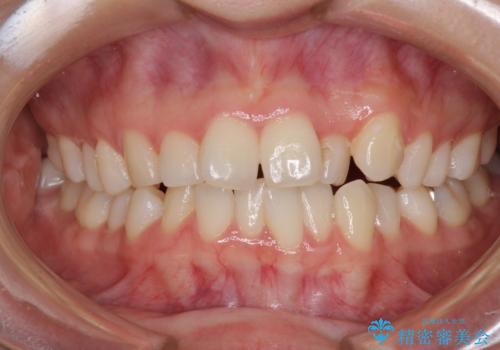

- 前歯のデコボコを気にして来院された患者様です。

前歯のデコボコはもちろん気になるところですが、舌の突出癖により上下の前歯に大きな隙間がある状態でした。

上下前歯が非接触である開咬は、インビザラインによる治療がお勧めではありますが、非抜歯矯正か抜歯矯正か悩む口元であり、途中抜歯矯正に切り替えたときに対応しやすいよう、ワイヤー装置にて治療を行うこととしました。